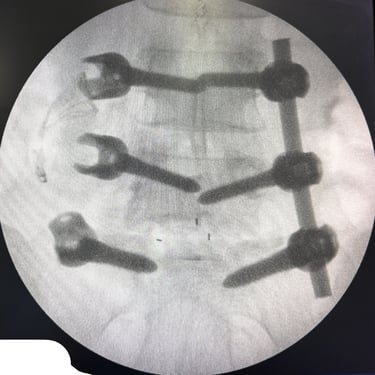

Manejo quirúrgico de la hernia lumbar con inestabilidad: enfoque moderno con FTP y TLIF

La hernia lumbar con inestabilidad vertebral es una patología frecuente que causa dolor lumbar persistente, ciática y limitación funcional, afectando la calidad de vida del paciente. Cuando el tratamiento conservador no logra resultados adecuados, la cirugía se convierte en la mejor opción terapéutica. La fijación transpedicular con tornillos (FTP) junto con la técnica TLIF (Transforaminal Lumbar Interbody Fusion) permite estabilizar la columna, descomprimir las estructuras nerviosas y lograr una adecuada fusión ósea. Este abordaje, especialmente mediante técnicas mínimamente invasivas (MISS), ofrece múltiples beneficios, como menor daño muscular, menor dolor postoperatorio y recuperación más rápida, facilitando el retorno temprano a las actividades cotidianas con mejores resultados clínicos.